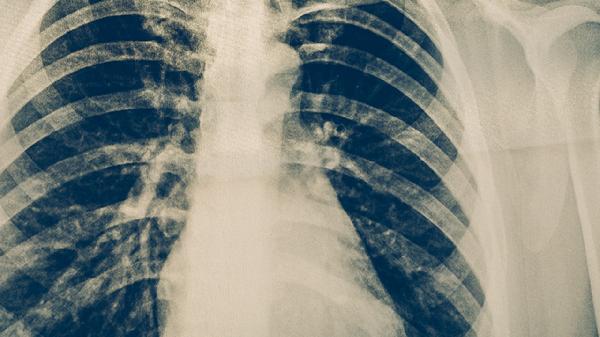

預防肺結核需建立多重防護體系。日常注意咳嗽禮儀,用紙巾遮掩口鼻后及時丟棄。高危人群可每年進行胸部X線篩查。出現(xiàn)疑似癥狀時避免自行用藥,應到結核病定點醫(yī)療機構進行痰培養(yǎng)和分子生物學檢測。保持規(guī)律作息與樂觀心態(tài)對免疫系統(tǒng)穩(wěn)態(tài)具有積極作用。